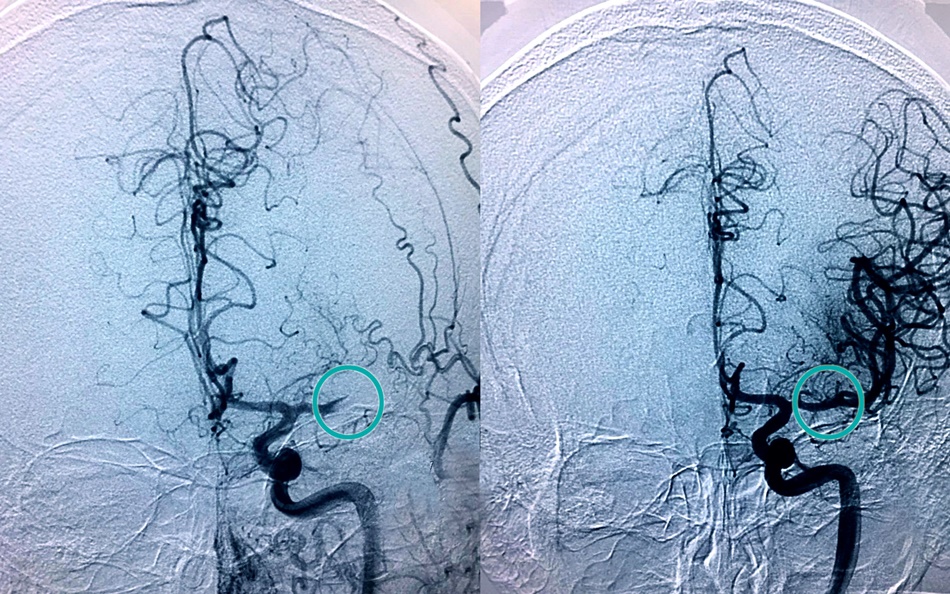

Hay dos formas de hacerlo, mediante medicación por vía intravenosa o extrayéndolo, lo que se conoce como trombectomía, una técnica para la que se requiere personal muy especializado, que llevan a cabo neuroradiólogos intervencionistas.